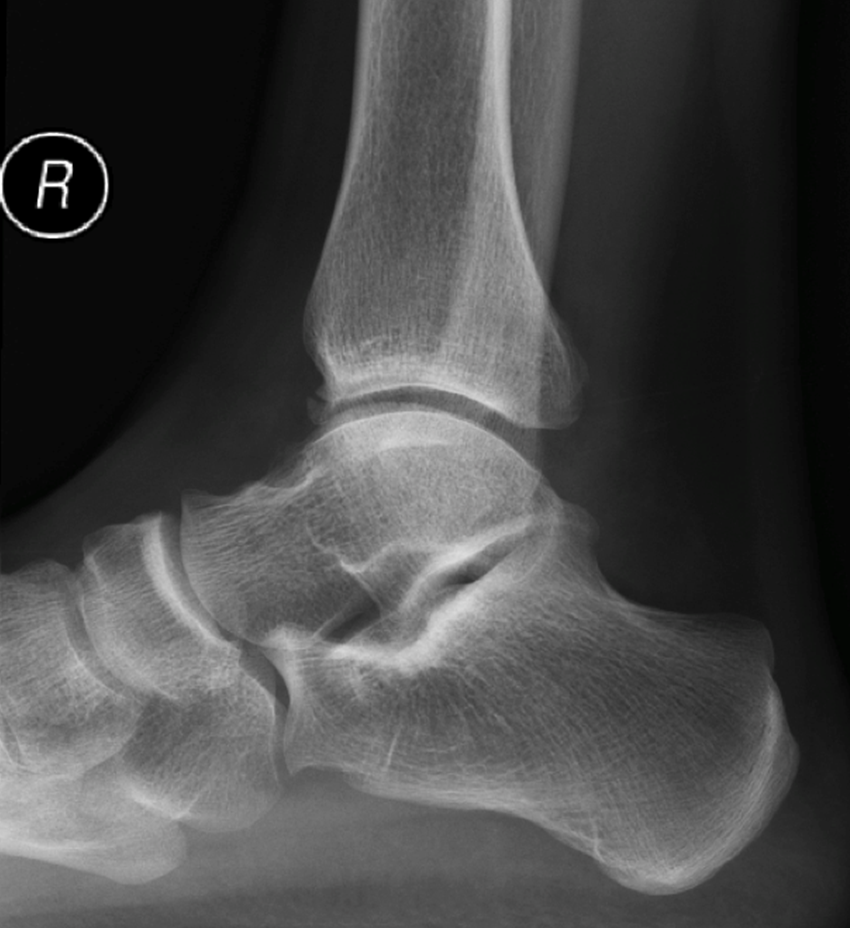

Geralmente o estudo é complementado com exames auxiliares de diagnóstico, como a radiografias em carga (pode logo identificar os osteófitos), ecografia e/ou a ressonância magnética.

• Osteófitos (traumatismo repetidos, podem levar à formação de osteófitos na região anterior do tornozelo, que reduz o espaço articular, causando impacto ósseo durante a dorsiflexão)

O conflito anterolateral do tornozelo é uma condição caracterizada pela dor na região lateral e anterior do tornozelo, causada pelo entrapment de tecido sinovial entre margem anterior da tíbia ou peróneo e o colo do astrágalo na posição de dorsiflexão do tornozelo.